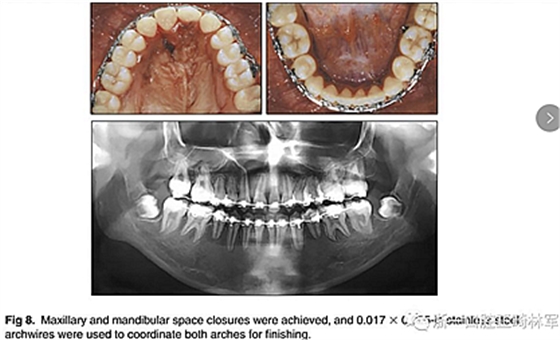

兩年半后,在上下牙弓上均實(shí)現(xiàn)了間隙關(guān)閉,并且使用0.017×0.025英寸的不銹鋼弓絲進(jìn)行咬合精細(xì)調(diào)整(圖8)。去除托槽后,上下頜采用舌側(cè)弓進(jìn)行保持(圖9)。